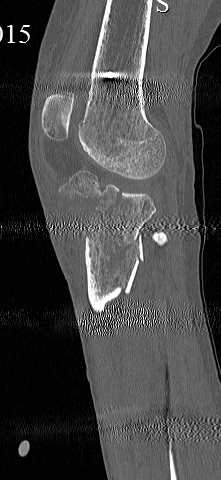

[Ortho] перелом проксимальной тибии + вывих бедра

Серия КТ сканов в аппарате